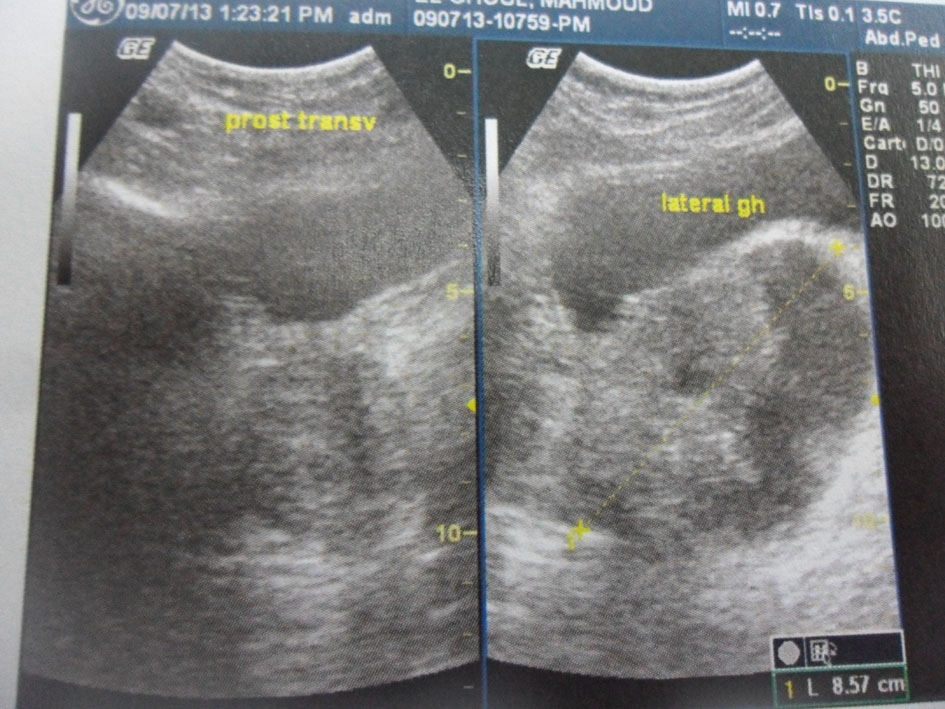

Pelvic ultrasound showed an 8.5 cm heterogeneous cystic and solid mass under the bladder and in the left periprostatic region (Fig. 1). A prostatic abscess or granulomatous prostatitis was highly suspected at first.

![]() Click for large image | Figure 1. Pelvic ultrasound. An 8.5 cm heterogeneous cystic and solid mass in the left periprostatic region. |